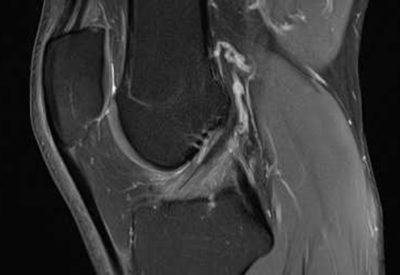

Hochwertige MRT-Untersuchung für maximale Diagnosesicherheit

Dann sind Sie bei uns richtig! Wir bieten Ihnen ein erfahrenes und spezialisiertes Ärzteteam, das MRT-Untersuchungen mit moderner Gerätetechnik durchführt. Unsere MRT-Untersuchungen sind optimiert und liefern hochauflösende Bilder, die eine maximale Diagnosesicherheit bieten.

Hochwertige MRT-Untersuchung für maximale Diagnosesicherheit

Dann sind Sie bei uns richtig! Wir bieten Ihnen ein erfahrenes und spezialisiertes Ärzteteam, das MRT-Untersuchungen mit moderner Gerätetechnik durchführt. Unsere MRT-Untersuchungen sind optimiert und liefern hochauflösende Bilder, die eine maximale Diagnosesicherheit bieten.